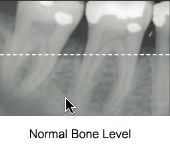

Periodontal disease is known for destruction of the supporting bone that is ultimately responsible for supporting your teeth and providing the support for your face and surrounding tissues. The aggressive bone loss involved in many types of periodontal disease can leave large areas of the tooth root without bony coverage and support. This can be compared to a block of swiss cheese where entire regions of a solid cheese block are missing. As these regions of bone “melt away” during the disease process, like a piece of ice melting, they reduce the bony support for the tooth itself. This degradation process decreases the foundational support required to carry the heavy stresses that are exerted on the teeth during daily chewing, swallowing, and other daily functions.

Bone grafting during conventional periodontal flap surgery provides the opportunity for the surgeon to stimulate new bone development in some of these regions if measures are undertaken before the disease progresses too far and before too much foundational structure is destroyed. Bone grafting techniques utilize various types of grafting materials to used to “stimulate” new bone development between existing bone and the adjacent tooth surface. The graft particles act as a scaffolding for new bone growth, actually allowing the body to eventually replace the graft material with natural bone produced by the patinet’s own development system. Sources of bone graft materials include bovine, porcine, human, and some synthetic materials. Each clinical situation calls for specific types of grafting and it is the decision of the surgeon what type of material will be used in a particular situation.